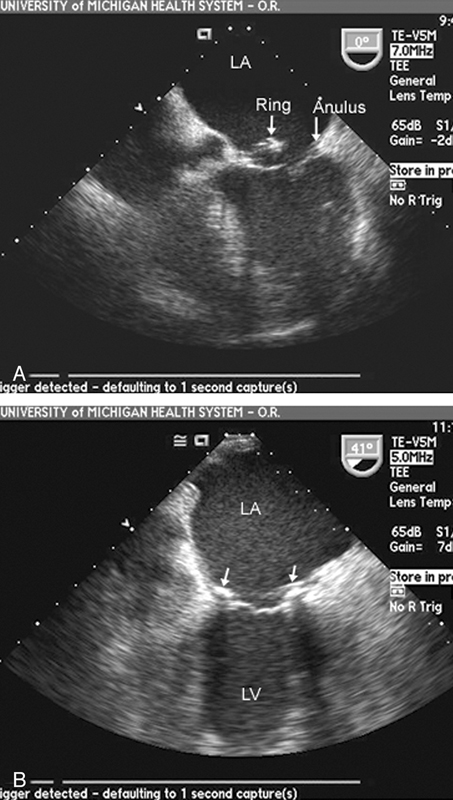

فحوصات تشخيصية لبعض امراض القلب والشرايين التاجية